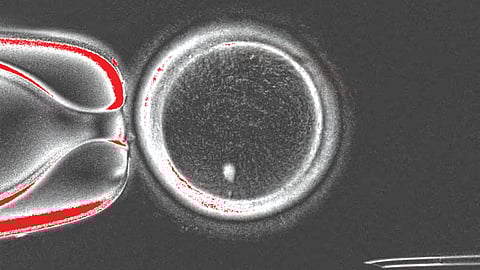

‘नेचर कम्युनिकेशन्स’ नावाच्या नियतकालिकात प्रकाशित झालेल्या या ‘प्रूफ-ऑफ-कॉन्सेप्ट’ अभ्यासात, संशोधकांनी सामान्य मानवी त्वचेच्या पेशींमधून केंद्रक, म्हणजेच पेशीचा तो भाग ज्यात बहुतेक जनुकीय माहिती असते, वेगळा केला. त्यानंतर हे केंद्रक, ज्याचे केंद्रक काढले आहे, अशा दात्याच्या अंड्यामध्ये (donor egg) प्रत्यारोपित केले. या प्रक्रियेतून संशोधकांनी एकूण 82 कार्यक्षम मानवी अंडपेशी ( immature egg cells) तयार केल्या, ज्यांवर नंतर प्रयोगशाळेत फलन (fertilization) केले गेले. या प्रयोगाचे यश म्हणजे, तयार झालेले अंडे हे त्वचेची पेशी देणार्या व्यक्तीसोबत डीएनए सामायिक (DNA shares) करते आणि ते दुसर्या व्यक्तीच्या शुक्राणूंनी फलित केले जाऊ शकते.

त्वचेच्या पेशींसारख्या सामान्य मानवी पेशींमध्ये 46 गुणसूत्र असतात. परंतु, लैंगिक पेशींमध्ये (अंड आणि शुक्राणू) याच्या निम्मी, म्हणजेच प्रत्येकी 23 गुणसूत्रे असतात. पोर्टलँडमधील ओरेगॉन हेल्थ अँड सायन्स युनिव्हर्सिटी (OHSU) येथील पथकाने एक अशी पद्धत विकसित केली, ज्यामुळे अतिरिक्त गुणसूत्र काढून टाकली जातात. त्यांनी नैसर्गिक पेशी विभाजनाचे अनुकरण करून 23 गुणसूत्रांचा एक संच बाहेर काढला, ज्यामुळे एक कार्यक्षम अंडपेशी तयार झाली. या प्रक्रियेला संशोधकांनी ‘मायटोमेओसिस‘ असे नाव दिले आहे. अभ्यासादरम्यान तयार झालेल्या अंड्यांपैकी 9% पेक्षा कमी अंडी भ्रूण विकासाच्या ब्लास्टोसिस्ट टप्प्यापर्यंत पोहोचली (फलनानंतरचे पाच किंवा सहा दिवस).